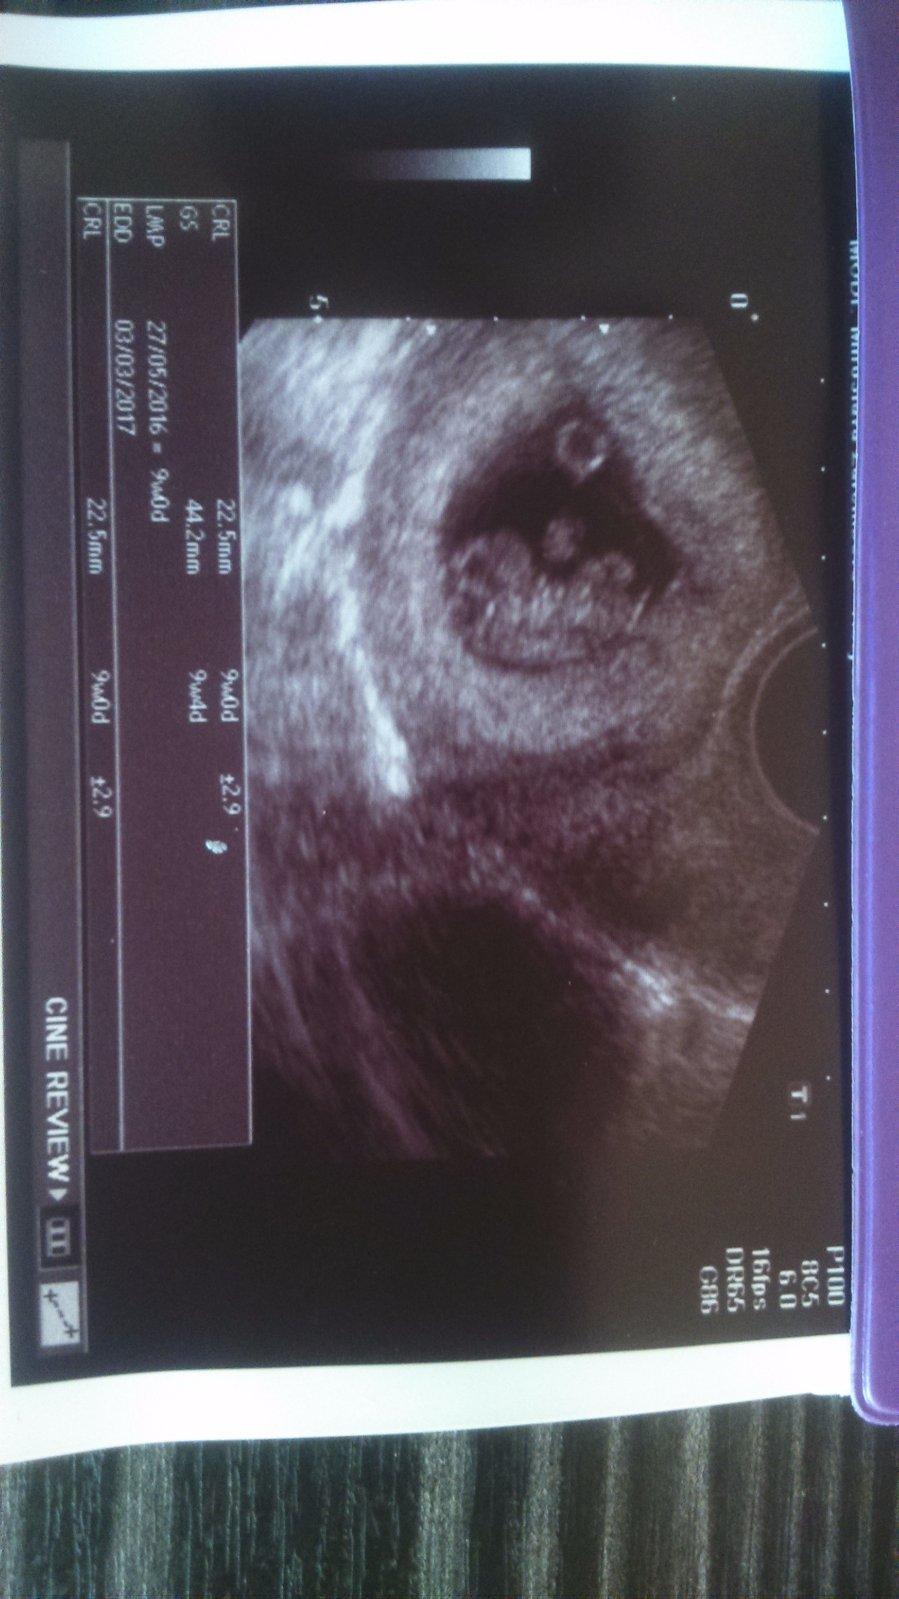

Ahoj holky 🙂 jdu vás trochu nabudit aby už se vám konečně podařilo najít ty // na testiku 🙂 dneska jsem byla na kontrole a tady je obrázek paní doktorka říkala že je čiperný už od brzkého rána a děsně se na ultrazvuku předváděl mimisek 🙂 dneska jsem 9+0... Tak když na vás prskani bacilu nestačí tak třeba obrázek zabere 🙂